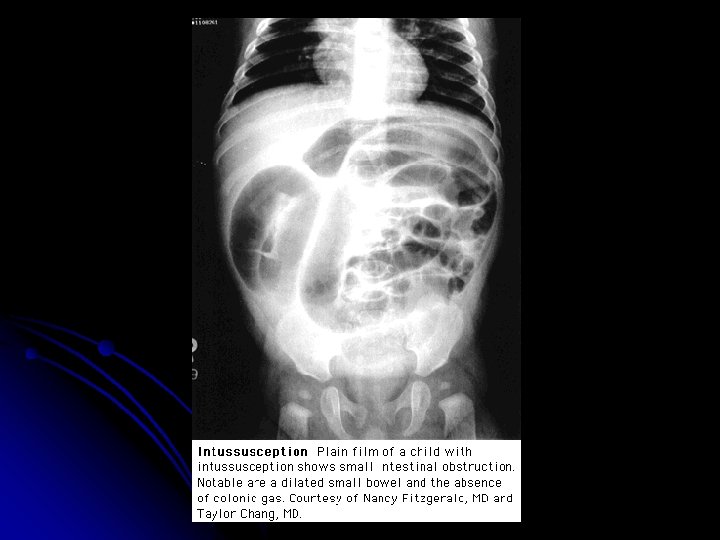

Diagnosis & Treatment l Abdominal plain films: l Crescent sign l Target sign l Ultrasonography: l Bull’s eye sign l Coiled spring sing l Target sign l CT scan (3 -1)

Intussusception Possible target sign in RUQ. Paucity of bowel gas suggestive of rightsided mass and bowel obstruction. X-ray diagnosis? 7 -month-old girl with skull fracture, lethargy, and vomiting.

Diagnosis & Treatment l (3 -3) High risk cases: l symptoms longer than 48 hours l Infant < 1 y/o (esp. <3 m/o) l children > 5 y/o, and when plain films show signs of intestinal obstruction Recurrance rate: approximately 10% l Surgery l